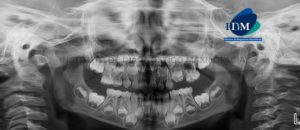

Paciente femenino de 07 años de edad, es referido al Instituto de Diagnóstico Maxilofacial – IDM para examen tomográfico por cirugía de odontoma. A la